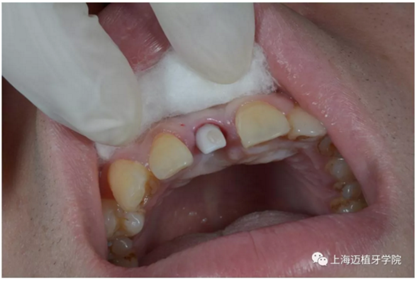

戴牙 最終修復(fù)效果